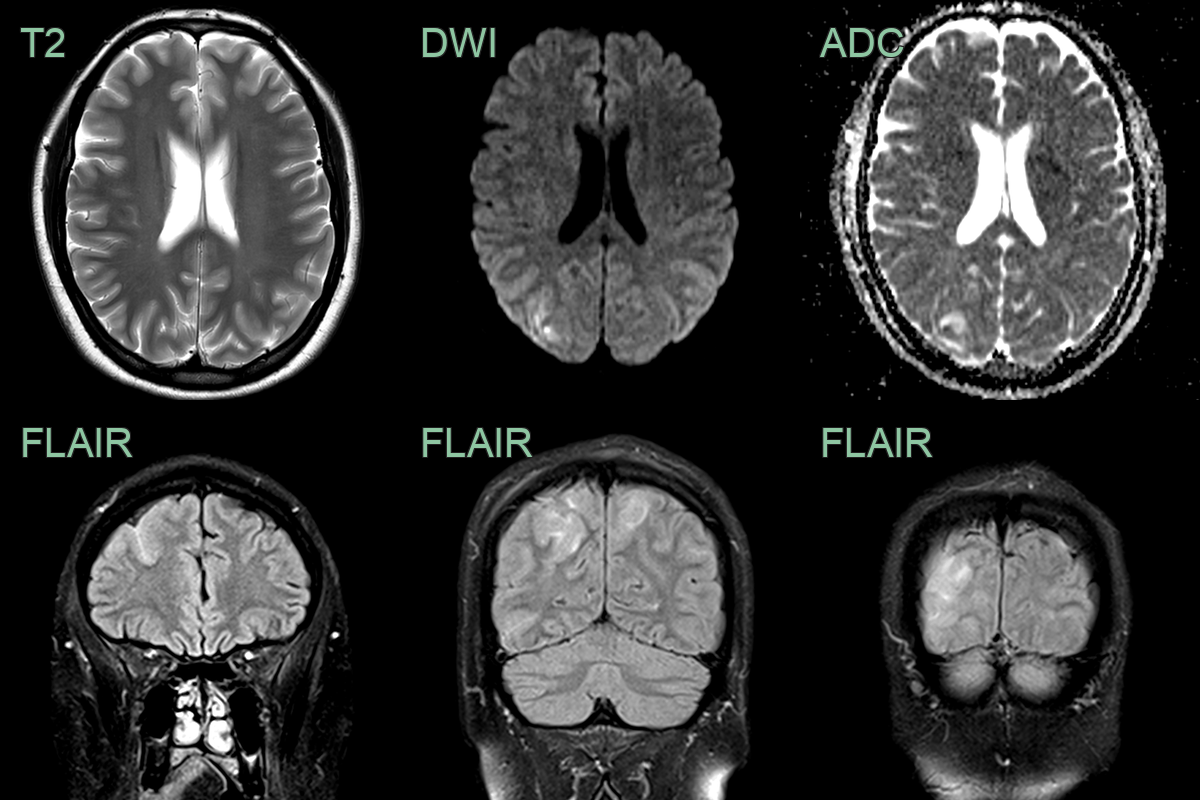

- MRI was performed after the patient developed an occipital headache, visual disturbance, and vomiting.

- MRI showed cortical and subcortical T2 and FLAIR hyperintensity and a trace of subarachnoid blood.